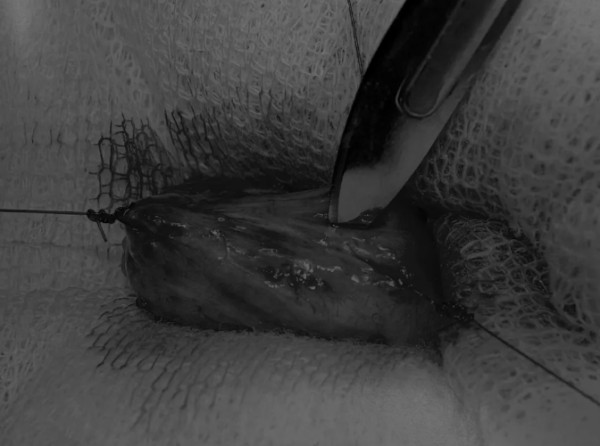

在牵引缝线之间选择血管扩张较差的区域用手术刀切开膀胱壁(图3)。在牵引缝合线之间用手术刀在血管不良的区域做切口。切开膀胱壁后,膀胱内的手术可按手术方案实施,例如取出结石(图4)。

戳下方点亮图片

文章详情图片

图3 避开主要的膀胱血管,做一个尽可能小的切口